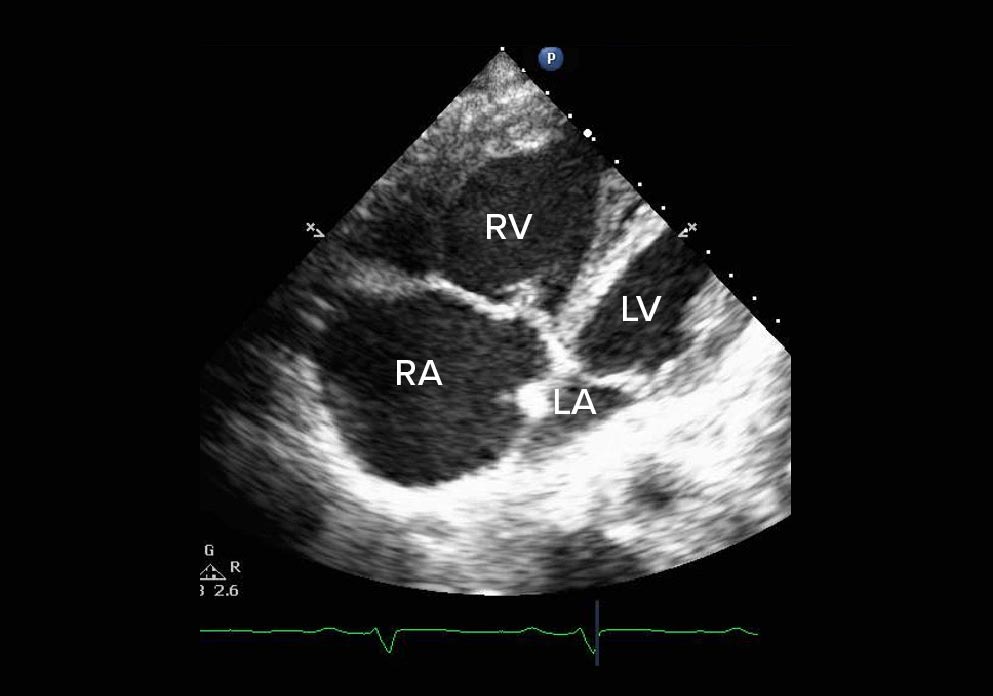

Echo imaging reveals right heart dilation

Echo provides essential visualization of right heart changes, aiding in detecting right heart dilation and dysfunction as the disease progresses.4,9

An apical 4-chamber view of an echo showing right dilation from PAH

Apical 4-chamber view

• Paradoxical wall motion septum

• Severe RV and RA dilation

Images courtesy of Anjali Vaidya, MD, FACC, FASE, FACP. Pulmonary Hypertension, Right Heart Failure & CTEPH Program, Temple University Hospital.